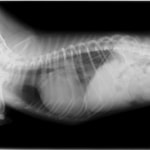

症例:【マルチーズ 12歳齢 去勢オス】

D:胸部レントゲン写真 正面像

E:胸部レントゲン写真 側面像

左側胸壁心尖部領域を最強点とするLevine 5/6の収縮期性心雑音が聴取された。

胸部レントゲン検査において重度の心拡大と肺水腫が認められた。超音波検査では、重度の僧帽弁閉鎖不全症、三尖弁閉鎖不全症、中程度の大動脈弁閉鎖不全症を合併していることが判明した。三尖弁逆流速度から肺高血圧症が示唆された。

ACE阻害薬、ピモベンダン、硝酸イソソルビド徐放剤、ベラプロストナトリウム、利尿剤としてフロセミドとスピロノラクトンを用いて治療を行った。